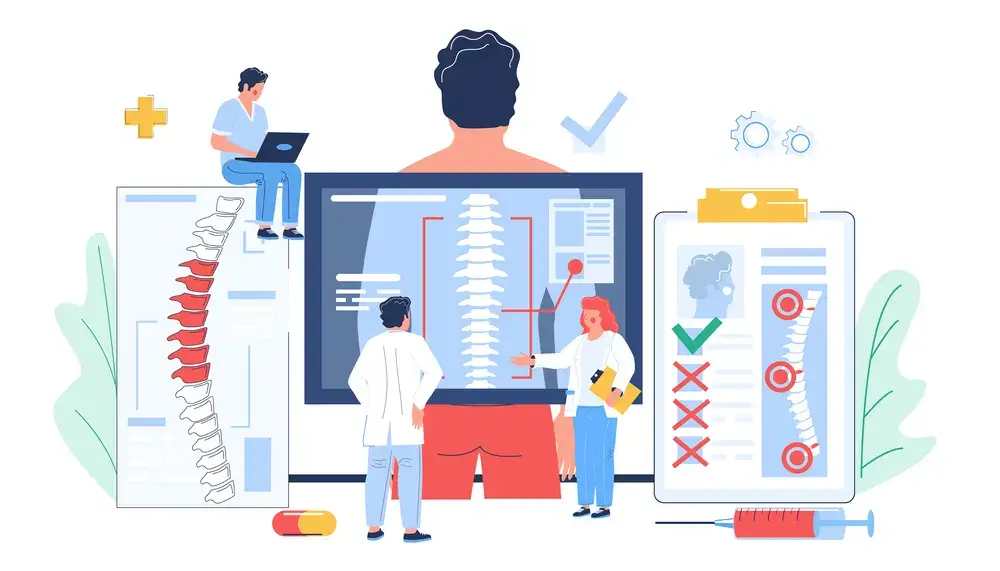

Chiropractic Services

Chiropractor Treatment: Georgetown Chiropractic Services

Finding a good Chiropractor who fully understands the rapidly changing health care needs, the most current ways and the approaches to addressing health problems can be very difficult. Our goal is that you will find this page very informative and helpful in learning more about Chiropractic services.

Chiropractor in Georgetown Ontario – 905-582-2360

HEAD, NECK & BACK PAIN | CHIROPRACTOR

HEAD, NECK & BACK PAIN | CHIROPRACTOR

Find relief for your head, neck, and back pain at our clinic with our chiropractor services. Many individuals throughout and around Halton Region suffer from head, neck, and back pains. These are called chronic pain issues which may be caused by any combination of factors. Poor posture, stress, disc problems or back injuries are common causes of these chronic pains. We are dedicated to helping you achieve a...